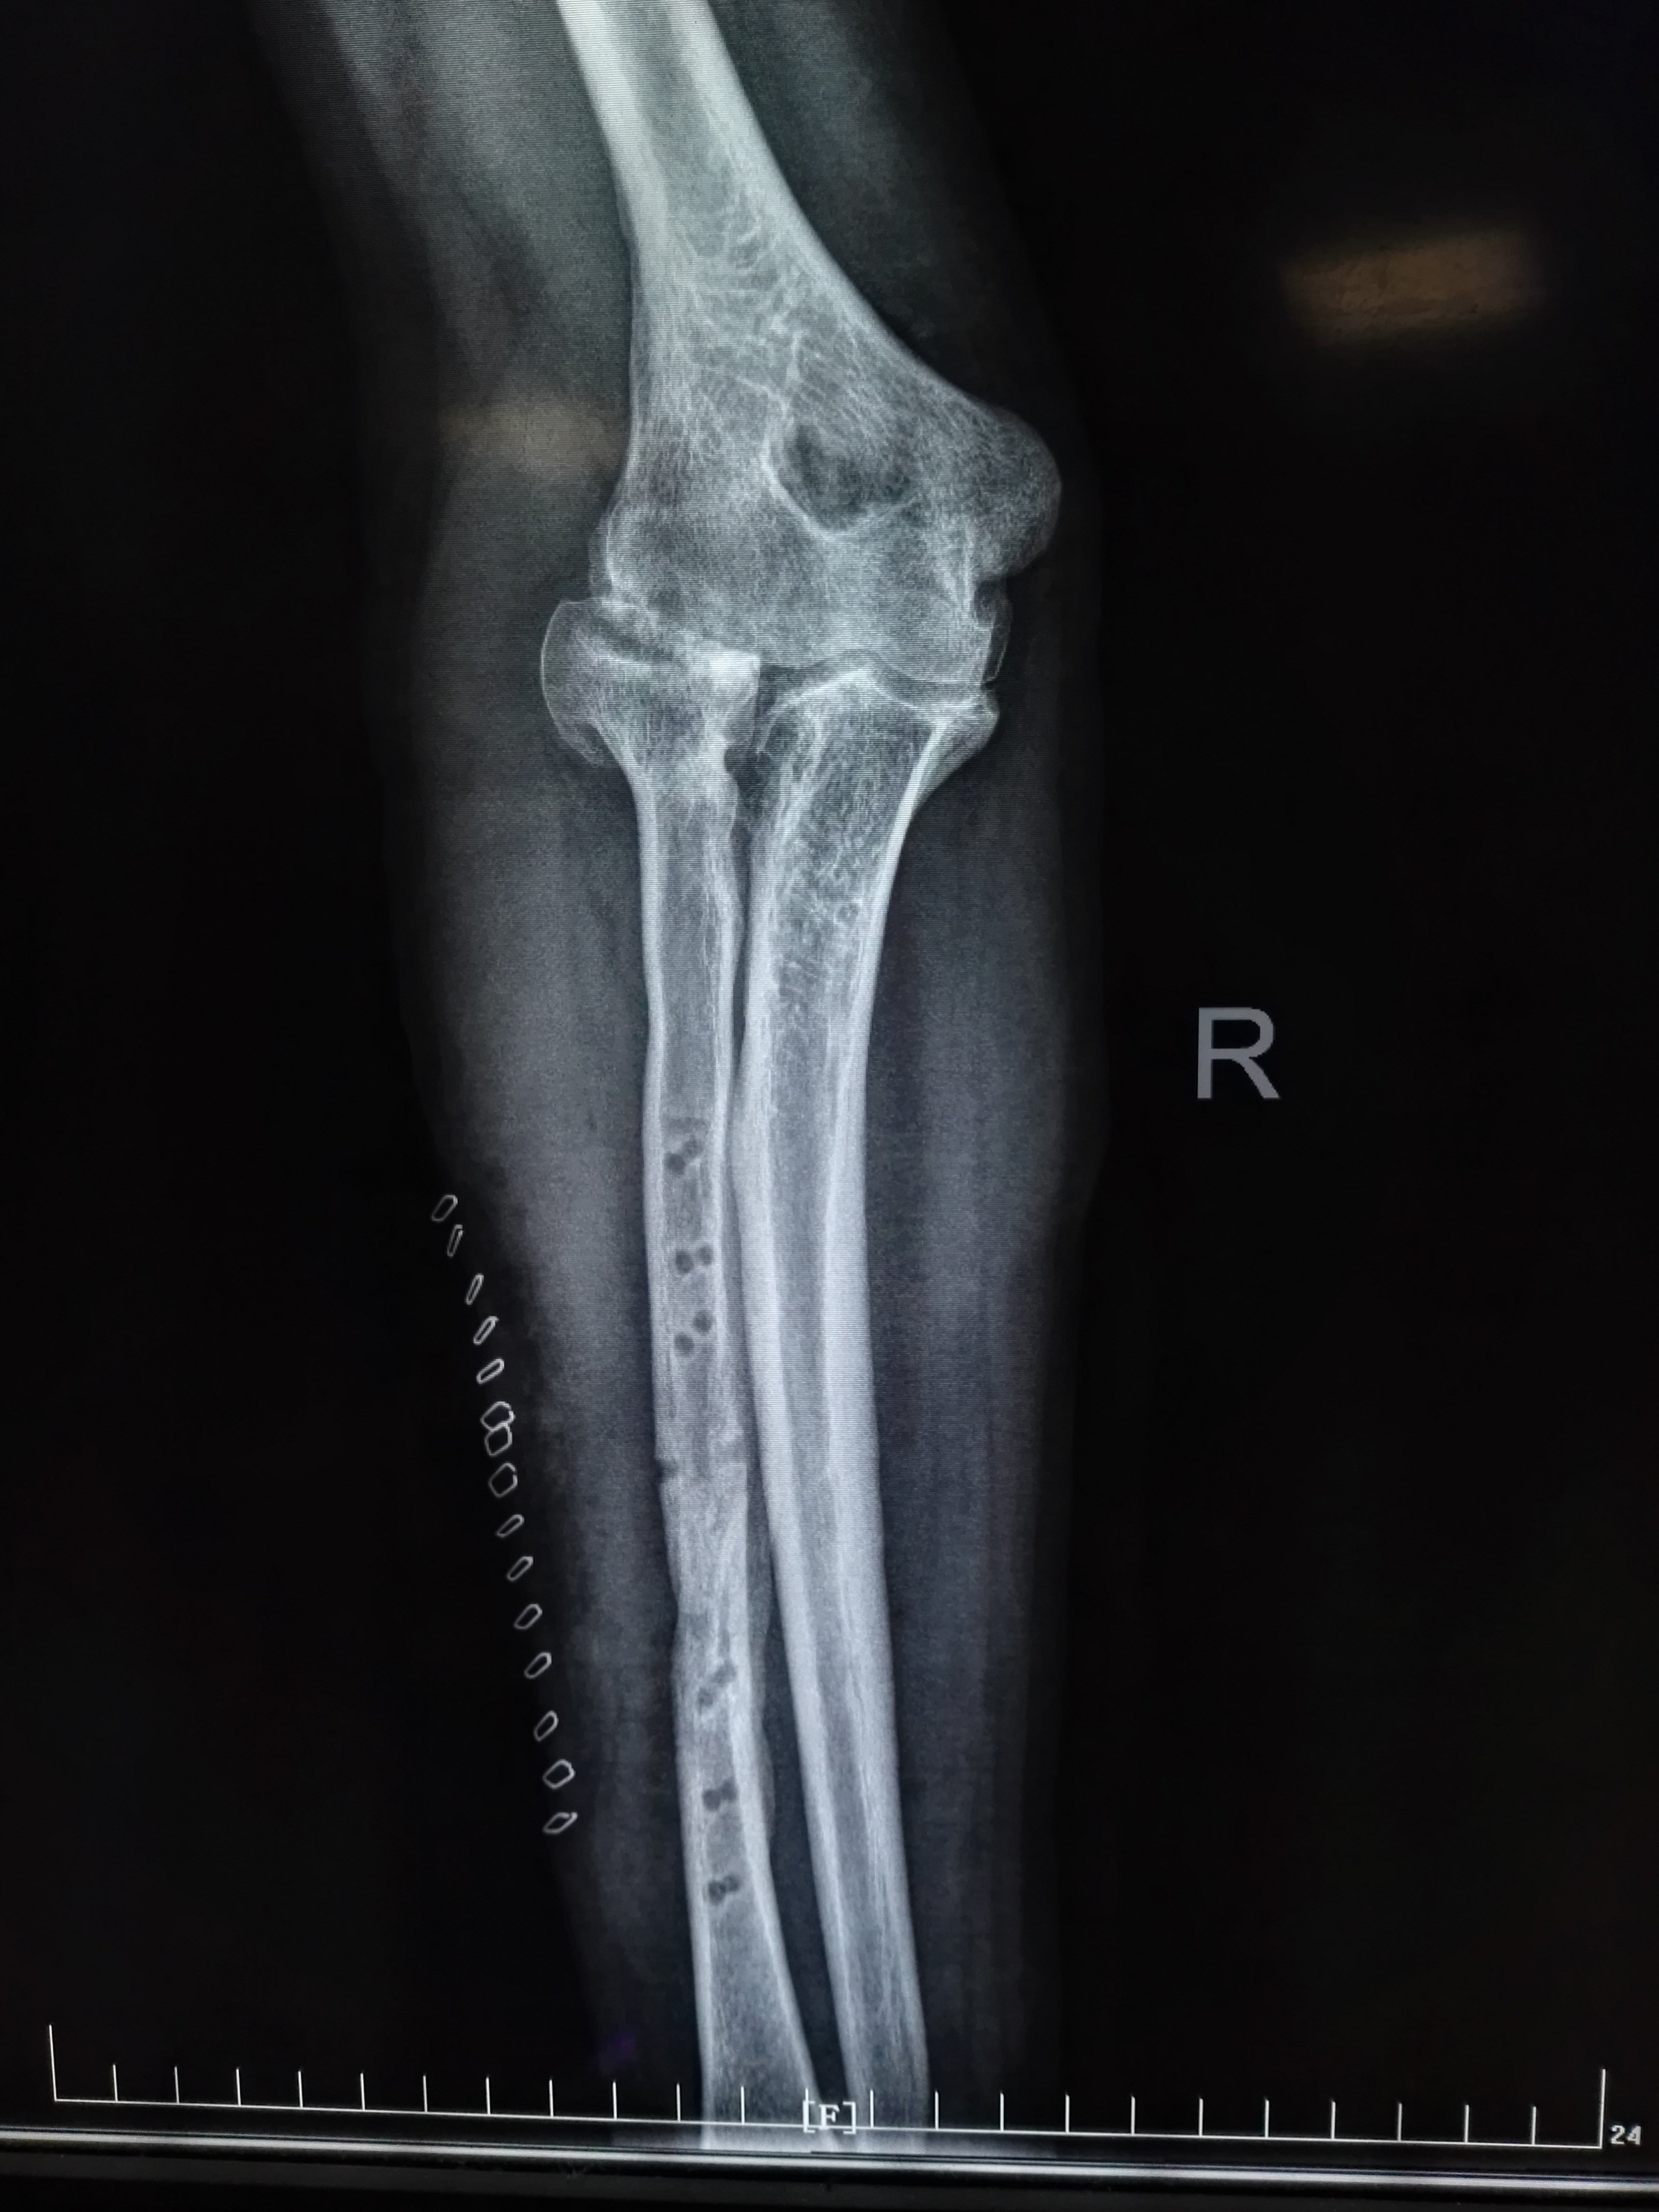

右侧尺骨骨折